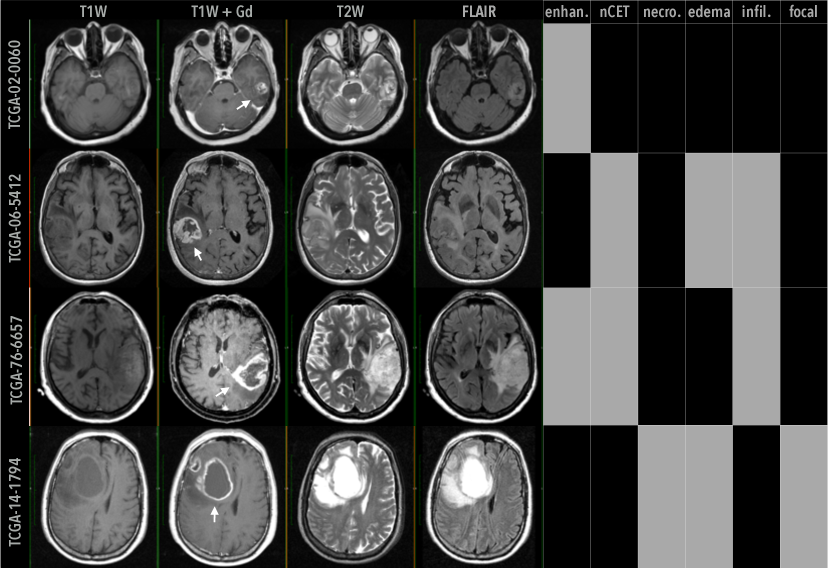

As a use case, we study radiogenomic associations related to human-understandable imaging traits in magnetic resonance imaging (MRI) scans from patients with glioblastoma (GBM). GBM is a grade IV malignant brain tumor with poor prognosis, and for which imaging is heavily used in diagnosis, prognosis, and treatment assessment. MRI traits like tumor enhancement, non-contrast enhancement, edema, and necrosis in Fig. 1, describe some of the visual, phenotypic variations between patients as they are diagnosed and treated. We present here extracted associations found by the radiogenomic neural networks using our approach, compare against previous work to show both new and consistent findings, and establish the radiogenomic associations’ clinical value in estimating patient survival over clinical or imaging traits alone.